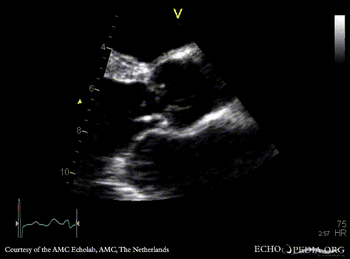

E00185.gif

E00186.jpg

A5CH: aortic valve vegetation Subcostal view: flow reversal in abdominal aorta